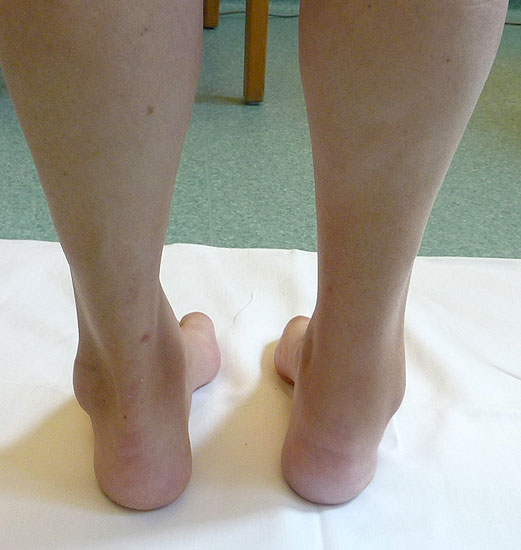

Inspektion des Patienten mit entkleideten Beinen (nicht nur mit hochgezogener Hose):

Inspektion im Stand

• von vorne

• von beiden Seiten

• von hinten

Folgende Befunde werden erhoben:

• Beinachse

• Form der Füße

• Morphologie der Beinmuskeln (Seitendifferenz, Waden distal dünn (Abb. 11), Narben)